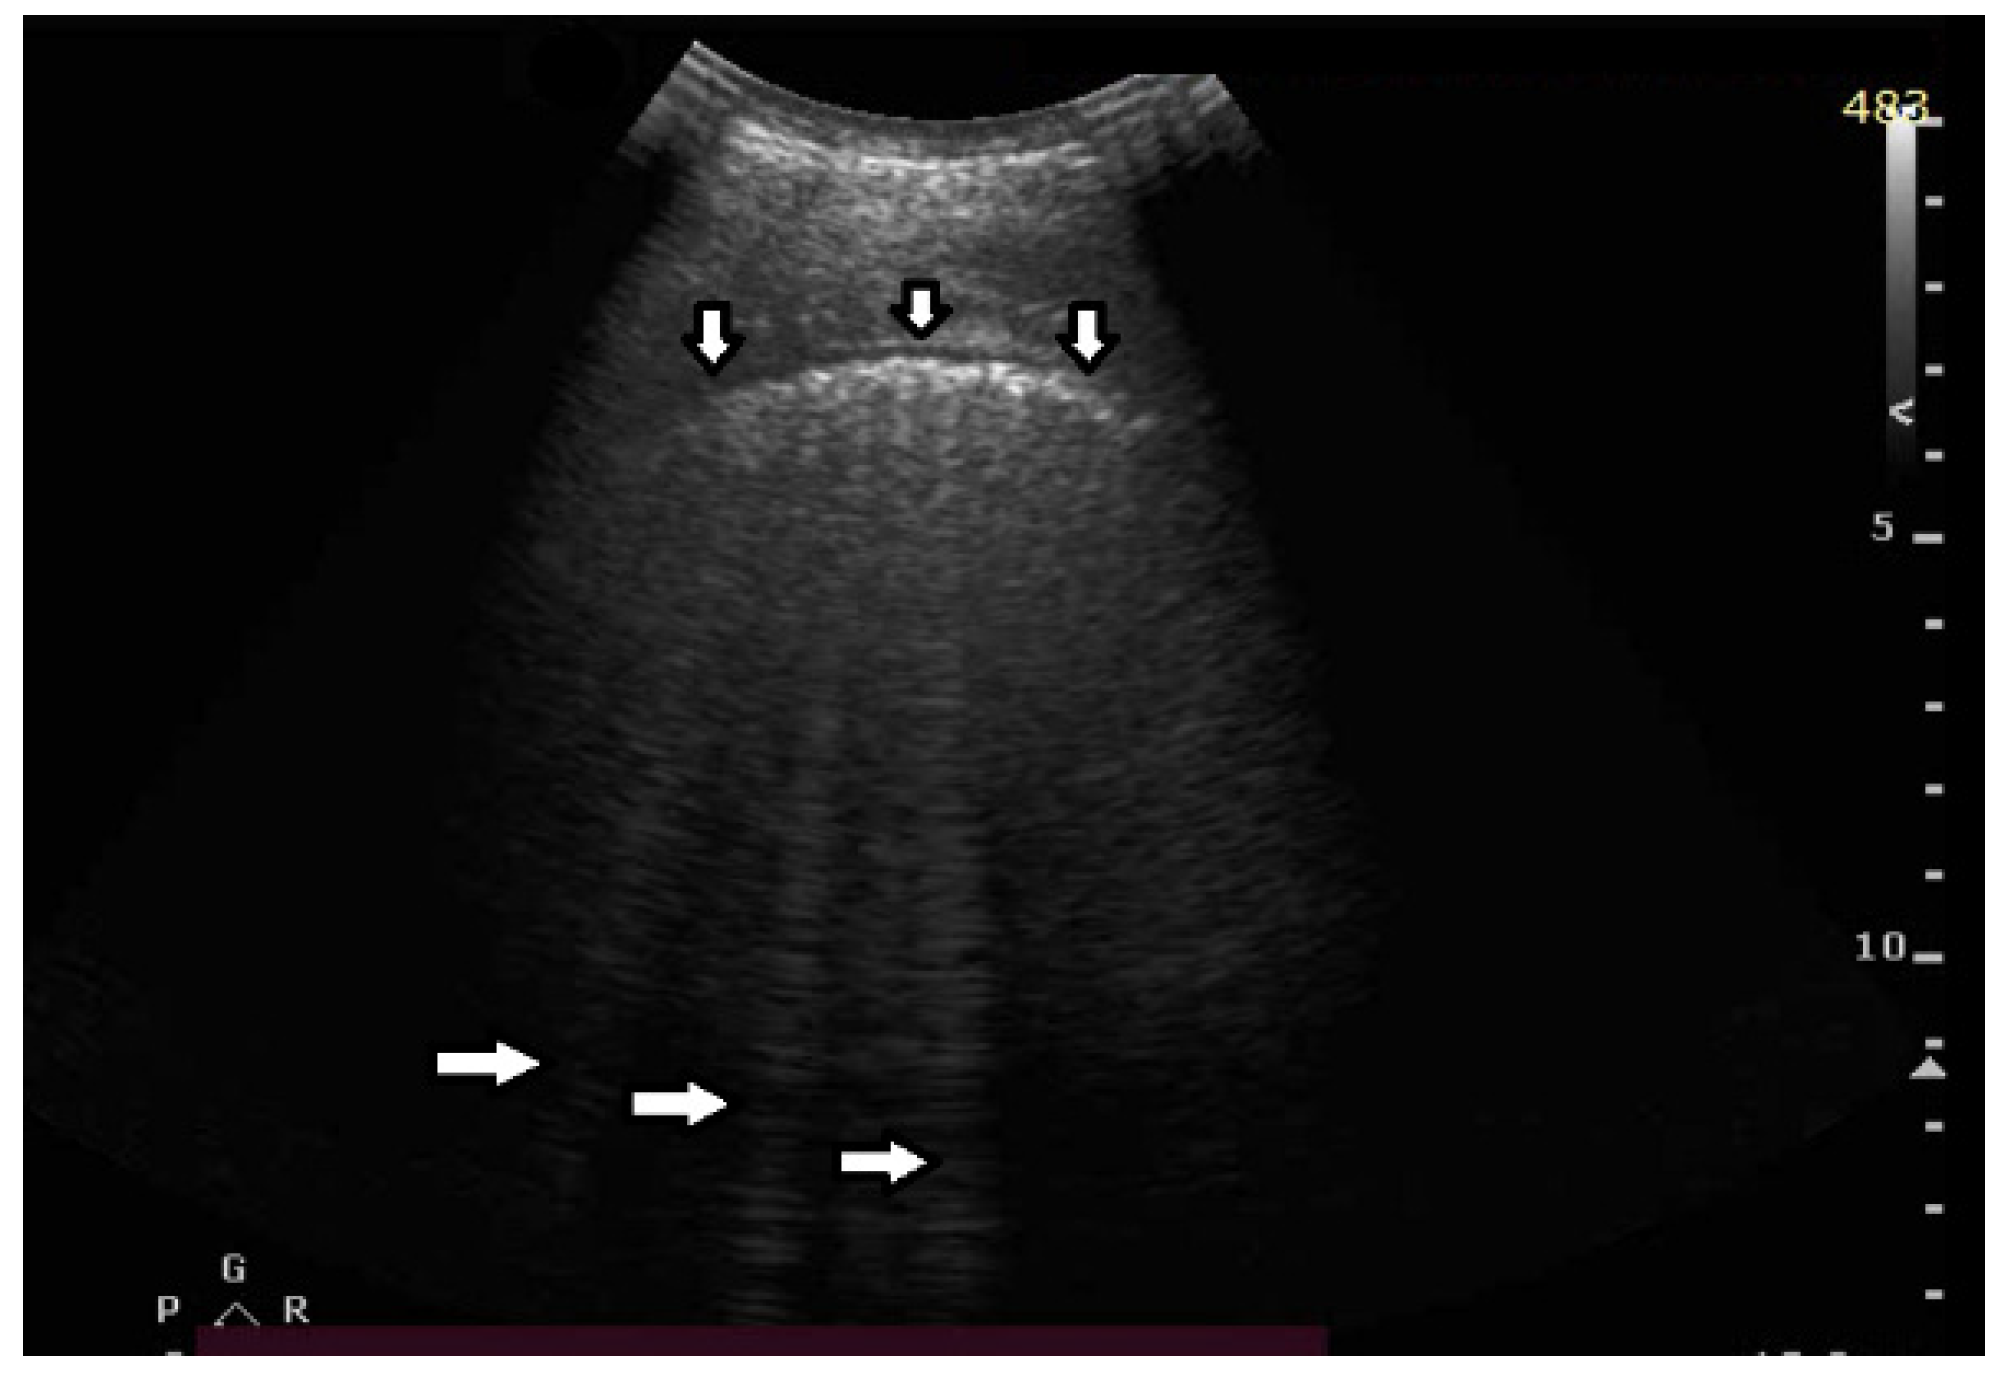

Based on clinical observations, we know that vertical artifacts can have different lengths, widths, and shapes (see Figure 5a–c). A modulation of artifacts is also often clearly perceived. Why are they so varied? What does this depend on?

Figure 5.

(a) Irregular, echoic pleural line (vertical arrows), long vertical artifact (left horizontal arrows), and shadow behind the rib (right horizontal arrows). The vertical artifact is classified as a B line since it originates from the pleural line and reaches the edge of the screen. Multiple small horizontal artifacts (named J artifacts by D. Lichtenstein) are visible inside the B line. (b) Smooth, regular, and echoic pleural line (vertical arrows), long vertical artifact, so called B line: narrow at the top and wide at the bottom (left and right horizontal arrows). (c) Smooth, regular, and echoic pleural line (vertical arrow), short vertical artifact, so called I line (left horizontal arrow and shadow behind the rib (right horizontal arrows).

- Answer 9:

Many types of acoustic traps exist, and, consequently, many types of vertical artifacts exist. Let us consider an isolated acoustic trap. It has its own volume and geometric shape. It is linked to the pleura plane by means of an acoustic channel (typically an interalveolar interstice), and this channel also has its own shape and size represented by its cross-section and length. Every single difference between two acoustic traps affects the visual aspect of the related artifacts. Moreover, you should never forget that even the imaging parameters (pulse central frequency and bandwidth, focus position, TGC, pulse amplitude, etc.) strongly affect the formation and the final shape of an artifact.